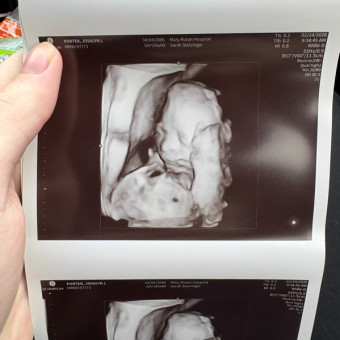

Thank you so much for visiting our baby registry and helping us celebrate the upcoming arrival of Wrenley KayLynn Daniels, who is expected to join us in July.